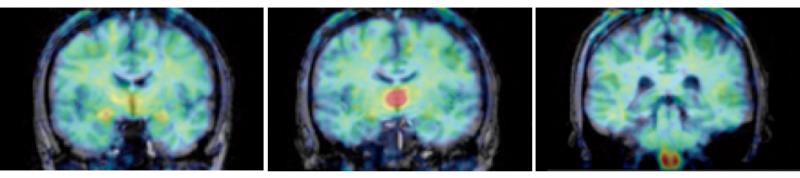

In these PET scans, taken from the front to the back of the head, color indicates the level of vorozole, a molecule that binds to the enzyme responsible for estrogen production in the brain (following the rainbow spectrum, red is the highest level, blue the lowest). These illustrate the regions found to have the highest levels of estrogen production (from left the thalamus, amygdala, and medulla oblongata's inferior olive), a pattern that was consistent across all six subjects and may be unique to humans.

Diagnosis, treatment and monitoring of estrogen-sensitive breast cancers will be simplified by the development of [11C]vorozole as a positron emission tomography (PET) tracer. This invention provides highly purified labeled vorozole for cancer diagnosis, treatment and treatment monitoring.